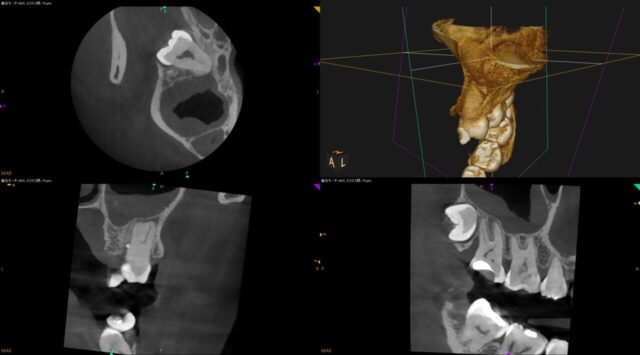

| 注意点 | この根管には偽根管と本来の根管とは違う、人為的な偽の根管を発生させる可能性。ニッケルチタンファイルを使用しプレカーブを付与して本来の根管へアプローチした。近心根にMB2が存在。weineの分類4型。非常に難易度が高い。マイクロスコープ、CTがあって診断可能。MB2は非常に狭窄している。 |

| 備考 | 本症例は動画で解説する。本症例は歯を抜かずマイクロスコープを使った根管治療で歯を残した。非常に丁寧に治療を行った。MB2が非常に狭窄しているため、通常施設では対応ができない。特殊なNITIファイルで対応する。MB2の根管充填非常に困難。本症例は歯冠部の破折が原因であった。 |